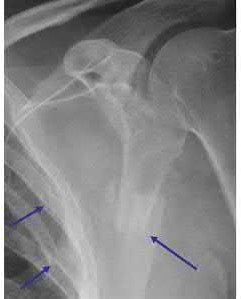

A 68-year-old osteoporotic female sustains a proximal humerus fracture. The AP radiograph is shown. According to the Hertel criteria, which of the following radiographic features is the most reliable predictor of humeral head ischemia?

Options:

- Anatomical neck fracture pattern

- Greater tuberosity displacement > 1 cm

- Metaphyseal head extension (calcar segment) less than 8 mm

- Varus angulation greater than 20 degrees

- Disruption of the medial periosteal hinge > 2 mm

Correct Answer: Metaphyseal head extension (calcar segment) less than 8 mm

Explanation:

Hertel et al. described radiographic criteria predictive of humeral head ischemia. The most reliable predictors include a metaphyseal head extension (calcar segment) of less than 8 mm, disruption of the medial hinge (>2 mm), and an anatomic neck fracture. Among the choices, the calcar segment length < 8 mm represents a highly predictive sign that the primary blood supply (the ascending branch of the anterior humeral circumflex artery and intraosseous vessels) has been severely compromised.